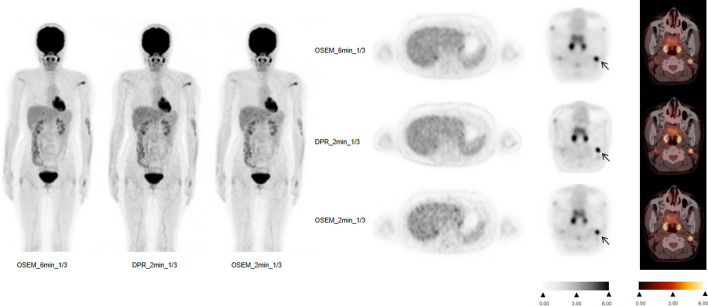

Methods: A total of 87 lymphoma patients (age, 45.1 ± 14.9 years) who underwent 18F-FDG PET imaging for during or post-treatment follow-up from November 2020 to February 2024 were prospectively enrolled. The patients were randomly assigned to two groups, including the 1/3 standard dose group and the standard dose group. Forty-four patients were injected with 1/3 standard dose (1.23 MBq/kg) and scanned for 6 min per bed and were reconstructed: ordered-subsets expectation maximization (OSEM) with 6 min per bed (OSEM_6 min_1/3), OSEM_2 min_1/3 and DPR_2 min_1/3. Forty-three patients were scanned according to the standard protocol (3.7 MBq/kg) and were reconstructed: OSEM with 2 min per bed (OSEM_2 min_full), OSEM_40 s_full and DPR_40 s_full. Additionally, the conventional 5-point scale measurement analysis was performed and DS for lymphoma were determined in different groups. Wilcoxon signed-rank test was used to compare the mean values of liver SUVmax and mediastinal blood pool (MBP) SUVmax in each group. Likert scale and DS were evaluated using Wilcoxon signed rank test.

Results: The patients with OSEM_6 min_1/3 and DPR_2 min_1/3 showed good image quality with 5(5,5) and 5(4,5) of Likert scoring, as well as the patients with OSEM_2 min_full and DPR_40 s_full. No significant difference was found between the OSEM_6 min_1/3 and DPR_2 min_1/3 groups in terms of liver SUVmax and MBP SUVmax (P = 0.452 and 0.430), as well as the patients with OSEM_2 min_full and DPR_40 s_full (P = 0.105 and 0.638). No significant difference was found between the OSEM_6 min_1/3 and DPR_2 min_1/3 groups in terms of lesion SUVmax (P = 0.080). There was a significant differences in lesion SUVmax between OSEM-2 min_full with DPR-40 s_full (P = 0.027). The DS results were consistent (100%) between OSEM-6 min_1/3 with DPR_2 min_1/3, and between OSEM-2 min_full with DPR-40 s_full, respectively.